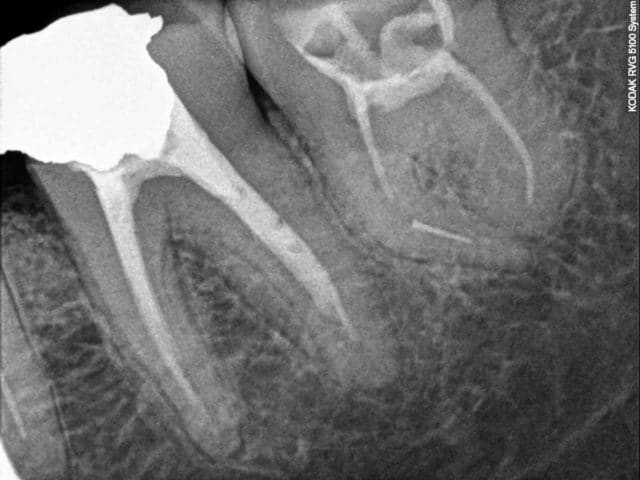

Patient vus à un mois d'intervalle pour des douleurs. Pas de devis miroboland, des CCM à 500 euros qui feront plaisir à santéclair ou à notre ministre de la mauvaise santé, secteur campagne.

Vus la premiere fois pour un debut d'infection sous 47 un samedi à la fermeture, demontage du screw post, allésage laissée ouverte avec une prescription puis retours chez mon confrére.

Puis un mois plus tard retour un samedi pour des douleurs suite à l'obturation de 46, endo metasonne, cône de 2%, canal ML et DL non preparés, démontage du cône DV avec le coton laissé dans la chambre.

Il n'ai pas besoin de faire des devis delirant ou de partiquer des tarifs de prothése excessifs pour mal faire notre travail.

Il a l'air doué ce dentiste ... il aurait pu faire la couronne sans faire l'endo sur la 6 et on fait semblant de pas avoir vu la fracture d'instrument sur la 7

Les patients sont mieux armés pour discuter de la réalité d'un devis gonflé, que sur la qualité des soins de bases. La 8 ne fait pas mal et si le ML ne saignait pas encore dans la dent "obturée", le traitement serait allé à son terme avec des CCM à 500 euro réalisées sur çà.